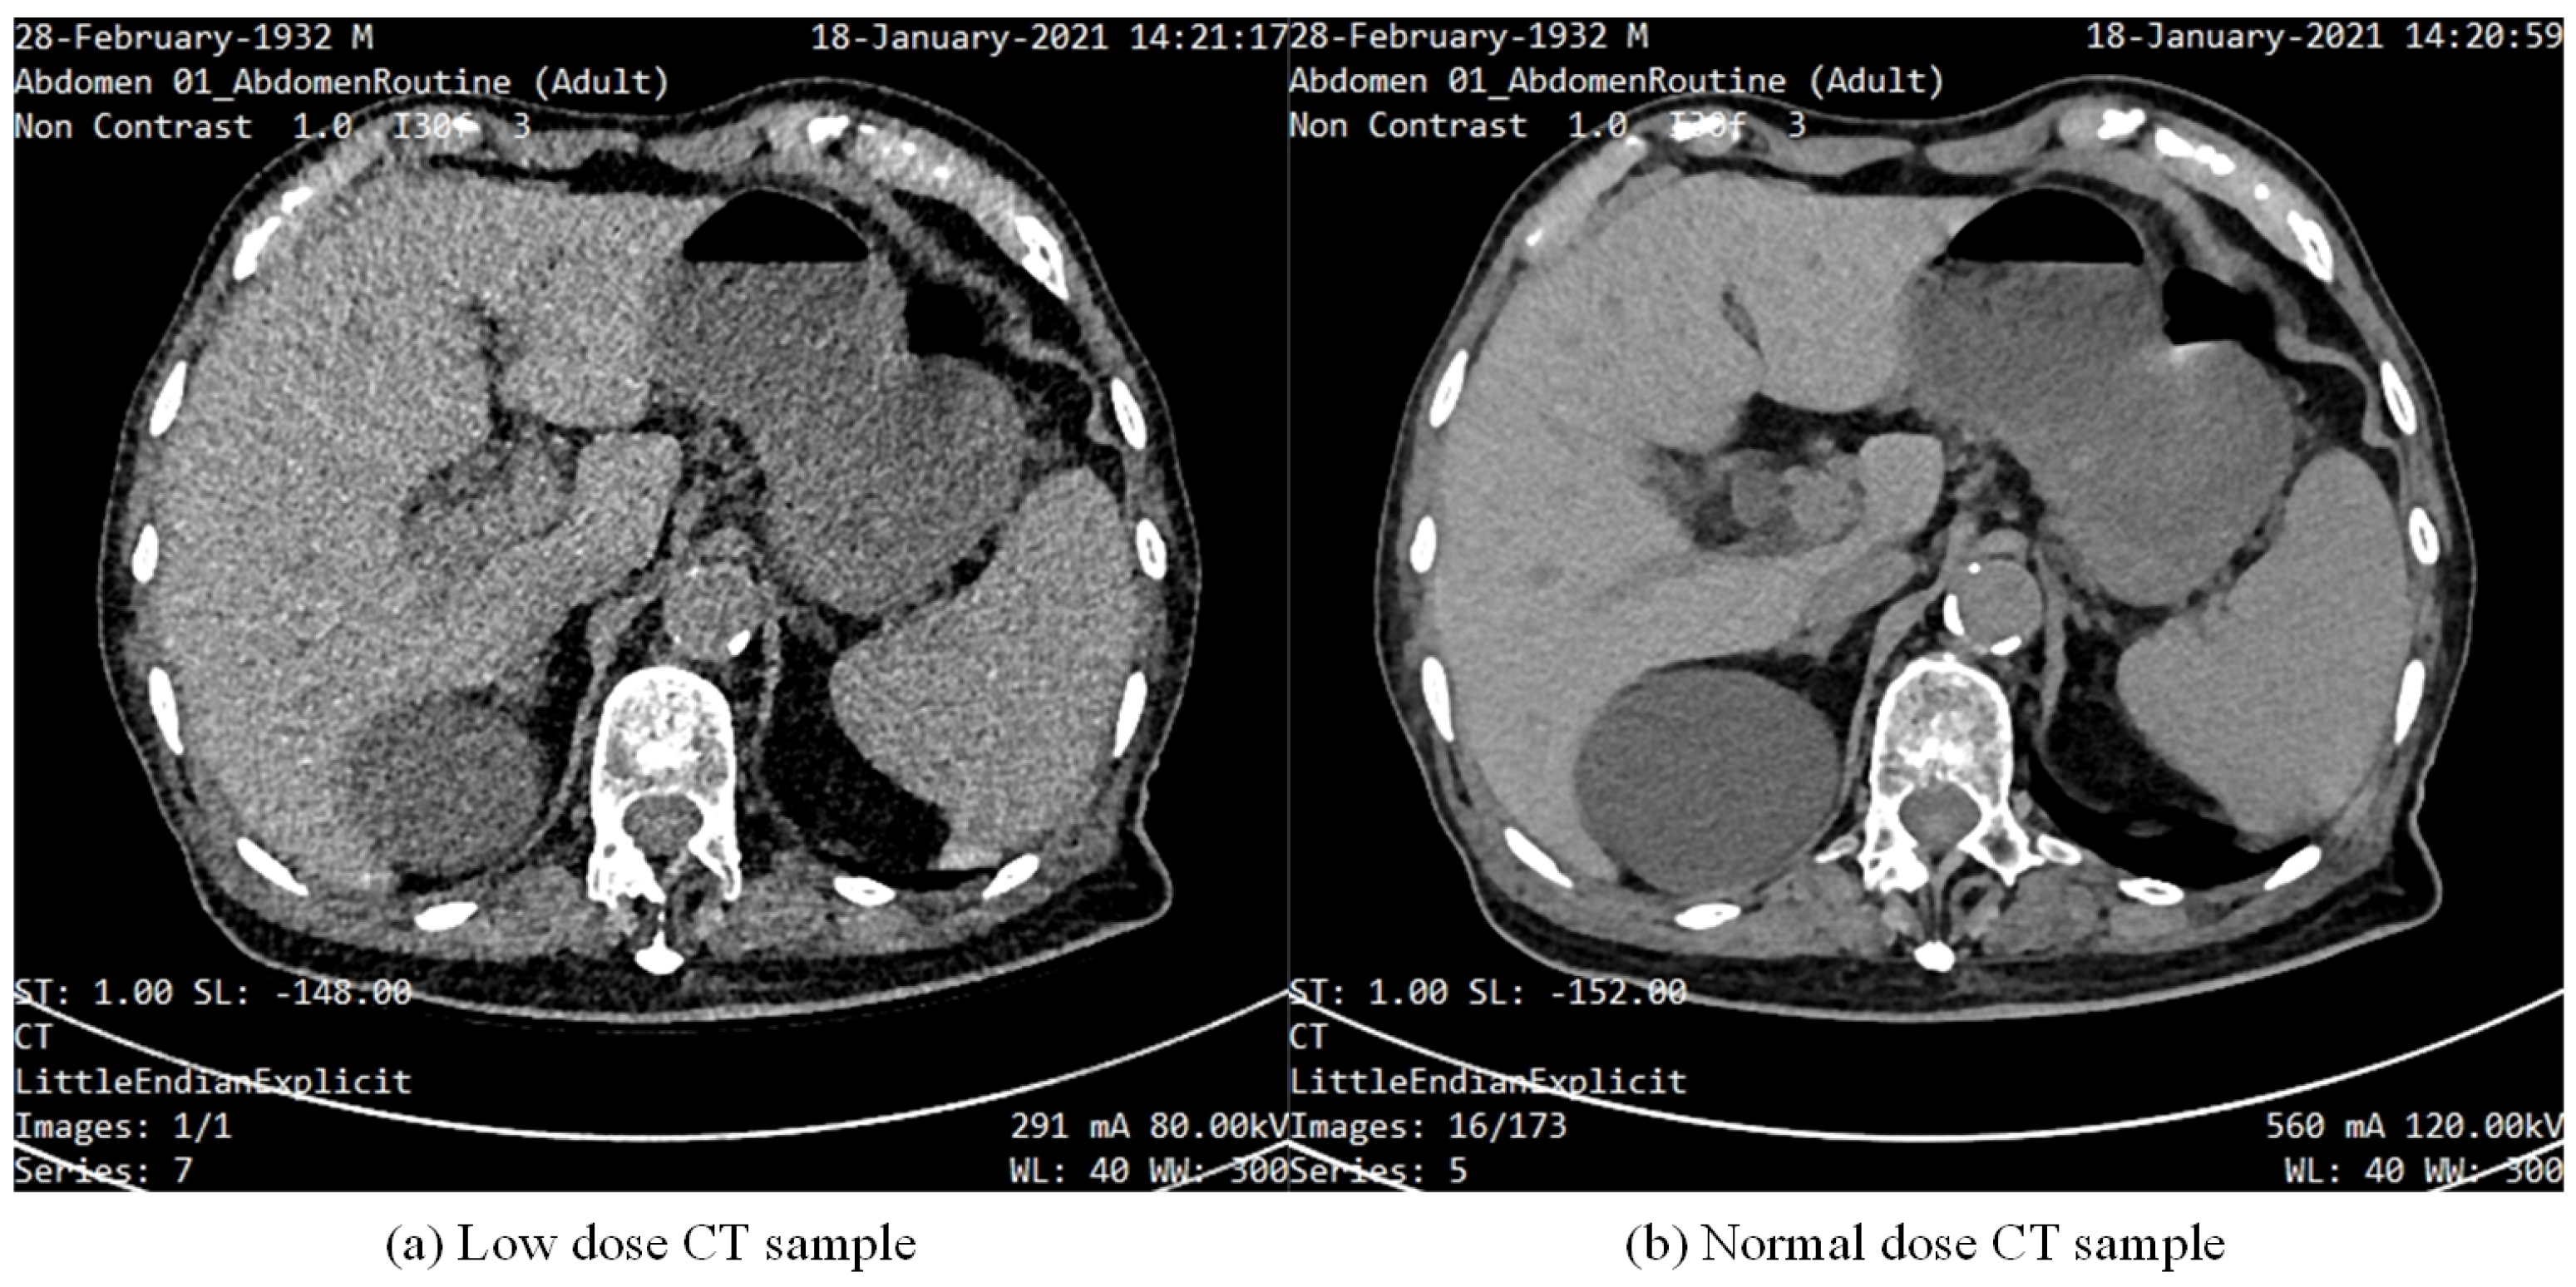

Figure 10 and Figure 11 illustrate the experimental results of our study on noise reduction in LDCT images using different methods. Figure 10 presents a side-by-side comparison of abdominal CT scans processed using different noise reduction methods. It includes (a) LDCT, (b) RED-CNN, (c) WGAN-VGG, (d) WGAN-AE, (e) WGAN-ATT-AE, and (f) NDCT. The WGAN-ATT-AE method shows a superior reduction in noise compared to other methods, closely approaching the quality of the normal dose CT. This is evident in the clearer visualization of anatomical structures. WGAN-ATT-AE maintains a high level of detail, similar to NDCT, while effectively reducing noise, unlike LDCT, which retains significant noise. Comparison with other methods: Compared to RED-CNN and WGAN-VGG, WGAN-ATT-AE and WGAN-AE provide better balance between noise reduction and detail preservation. WGAN-ATT-AE offers the most visually coherent and detailed image among the tested methods.

Figure 10.

Comparison of LDCT image denoising results using different methods.

The proposed WGAN-ATT-AE method demonstrates superior performance in both noise reduction and detail preservation, as seen in the overall comparison and the enlarged view. This visual evidence suggests that WGAN-ATT-AE is highly effective for enhancing the quality of LDCT images, potentially improving diagnostic accuracy while maintaining the advantages of low radiation exposure. These visual comparisons highlight the significant improvements achieved by our proposed method in terms of noise reduction and image quality enhancement, making it a promising tool for clinical applications in LDCT imaging.

Figure 11 shows an enlarged view of a specific region from the same set of abdominal CT scans used in the first image, focusing on the details provided by each method. The region in the LDCT image shows a significant amount of grainy noise, which obscures finer details and makes it difficult to interpret anatomical structures accurately. While RED-CNN reduces some noise, it still leaves a considerable amount of granularity, and some details are smoothed out. The WGAN-VGG method reduces noise effectively but introduces a slight blurring, which could affect the clarity of fine structures. This method provides a clearer image than the previous methods, with better detail retention and reduced noise. Our proposed method shows the best performance, significantly reducing noise while preserving fine details and textures, closely matching the quality of the NDCT. As the ground truth, the NDCT image presents the highest quality with minimal noise and clear anatomical details.

We conducted qualitative and quantitative analysis, and we compared the effects of the proposed methods (WGAN-AE, WGAN-ATT-AE) and the baseline method (WGAN-VGG) on locally enlarged images. The results show that the important anatomical structure and detailed information in the image can be effectively maintained while reducing noise, while the baseline method shows a greater degree of information loss. This finding further validates the superiority of the proposed method in maintaining image quality and highlights its potential application value in clinical diagnosis. The proposed method can better maintain detail information and structural integrity in locally enlarged images, and presents a clearer and more accurate enlargement effect compared with baseline methods. This finding highlights the superiority of the proposed method in image enhancement and provides more reliable support for clinical diagnosis, providing a further comparison of the performance of different methods in preserving image details and structure.

In conclusion, the interpretation of the local magnification results in CT images in the comparative experiments provides a comprehensive evaluation of the performance of the proposed method in image enhancement tasks and highlights its superiority in maintaining image details and structural integrity. These findings not only help to verify the effectiveness of the proposed method, but also provide an important reference for its application in clinical practice and provide useful inspiration for future research and technology development.